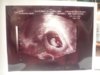

USG naszych Pociech

a to moje maleństwo:D